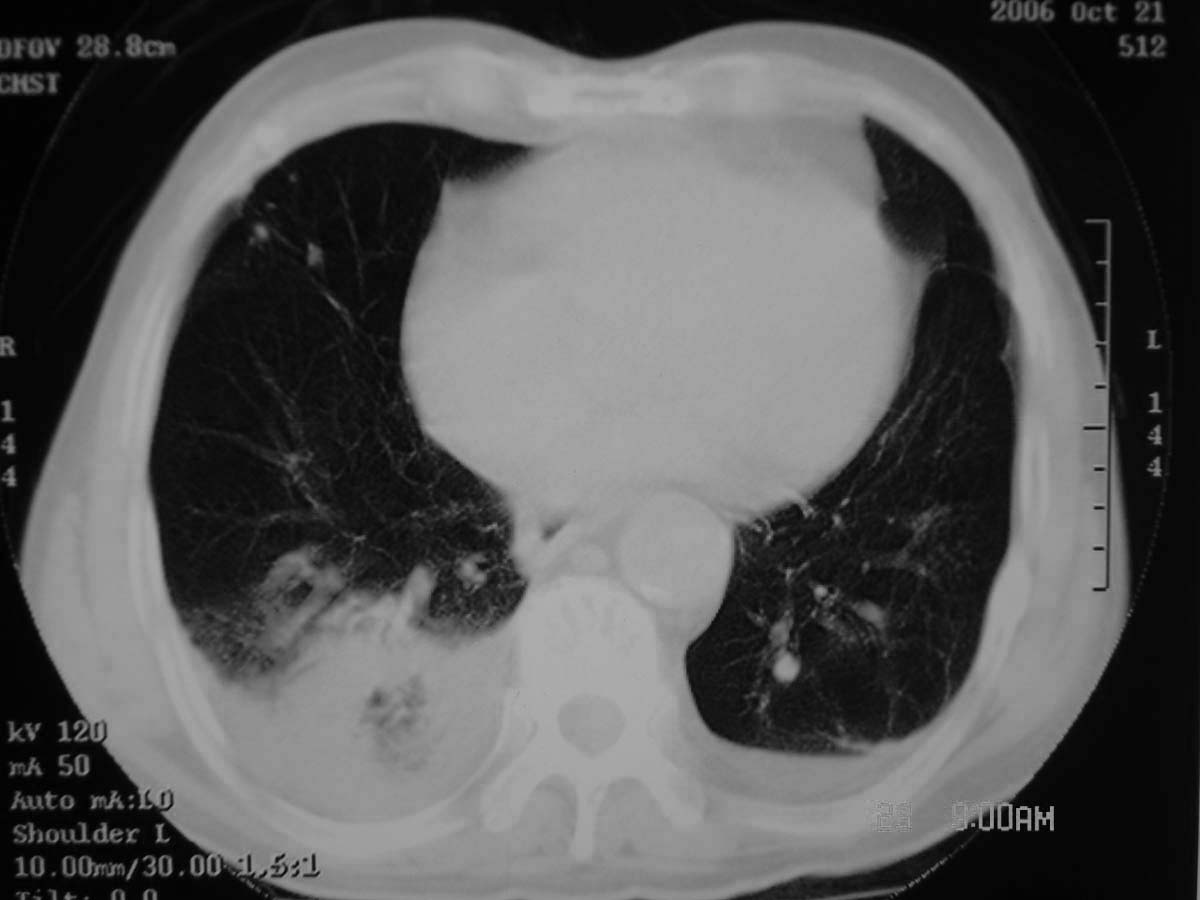

以下是引用守望可可西里在2006-11-23 14:33:00的发言:[br][br] 糖尿病病人很容易继发结核,病人又有双侧胸膜增厚、粘连、胸腔积液以及双上肺的斑片状、条索状影结核病灶影,以一元论考虑,右下肺病变首先考虑干酪性肺炎,可以正规抗炎治疗后复查,排除一般的肺炎。